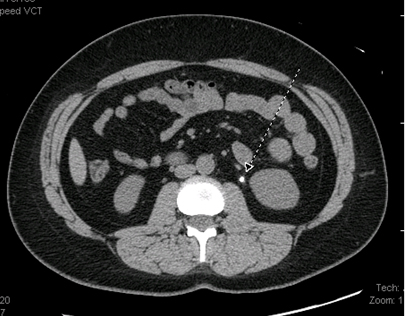

Tomografia computadorizada (TC) abdominal: pode ser realizada se houver suspeita de doença inflamatória no abdome (por exemplo, apendicite, pancreatite), principalmente se essa suspeita for reforçada por dados de exames laboratoriais, como contagem leucocitária elevada ou aumento de enzimas pancreáticas.[80] Também pode ser solicitada se houver suspeita de obstrução, torção ovariana, neoplasia maligna ou nefrolitíase. Em casos de suspeita de nefrolitíase, não deve ser usado contraste intravenoso.[Figure caption and citation for the preceding image starts]: Tomografia computadorizada (TC) do abdome com pequena calcificação em área do espaço ureteral esquerdo, correspondendo à presença de nefrolitíaseDos acervos do Dr. R.A. Gomez-Suarez e Dr. J.E. Fortunato; usado com permissão [Citation ends].